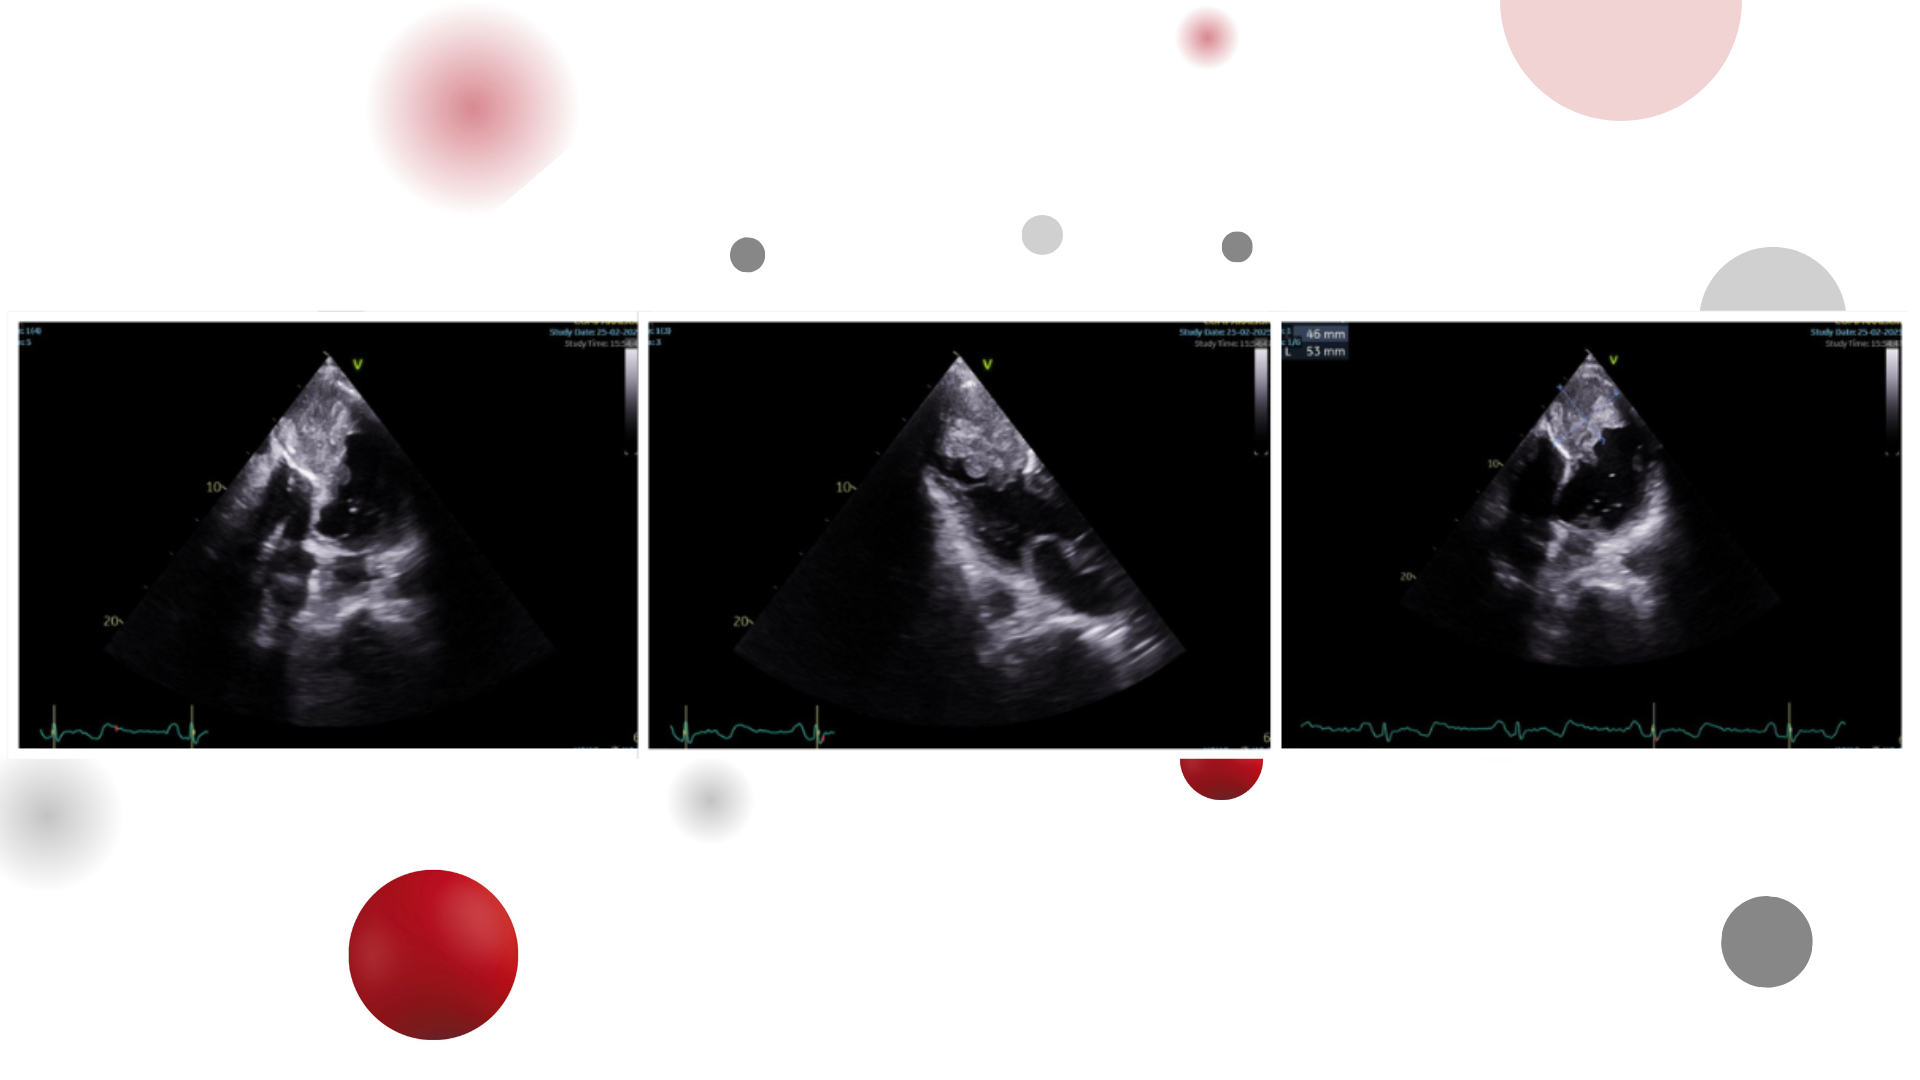

Image of the week 18 March 2026

Doctor Mohamed Mounir Nesnassi

Doctor Inasse Bargach

Doctor Taha Hassani